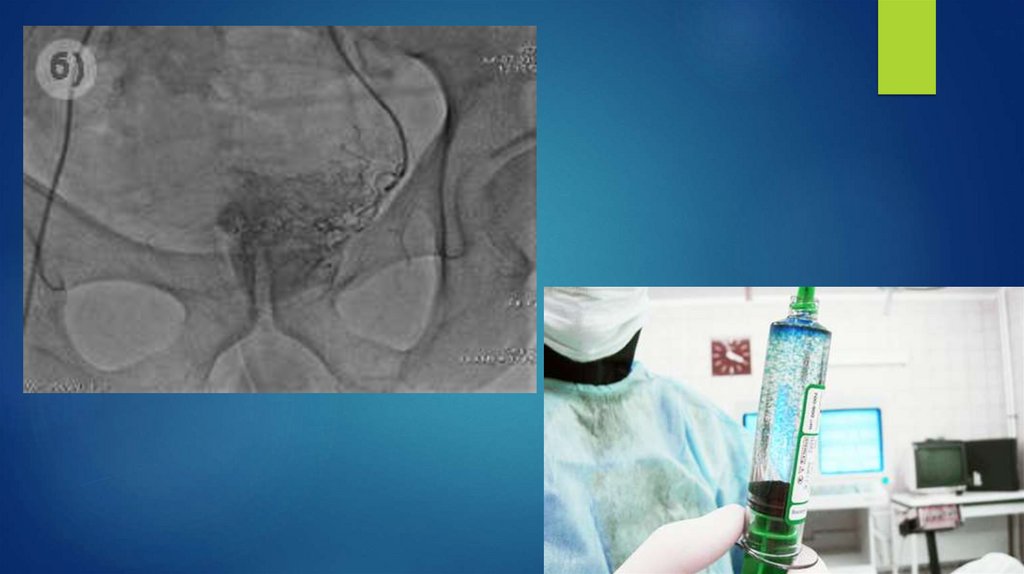

Ангиография

Ангиография яичковой вены

Камни почек

57. Ангиография

59. Ангиография яичковой вены